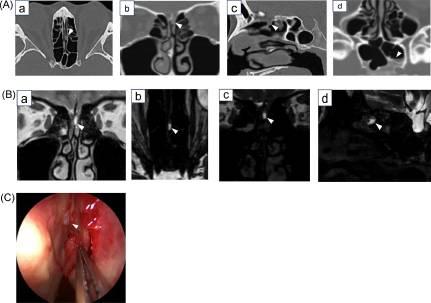

患者进行了头部CT和MRI检查。头部CT显示左侧嗅裂内有软组织密度,与左侧筛板相连,左侧蝶窦内有气液平面。头部MRI在冠状T2WI上显示左嗅裂有高信号强度,提示有液体成分。3D-MR脑池造影也显示左嗅裂中有液体信号,但其与蛛网膜间隙的连续性尚不清楚(图2A)。

术中(内窥镜脑脊液漏修复)在左上鼻甲和鼻中隔之间发现脑膜膨出,并观察到脑脊液漏。嗅裂中的瘘管大小约为1-2mm。脑脊液漏闭合后,鼻腔分泌物消失;然而,颅内压升高的症状复发,1个月后进行了腰腹腔分流术。

图2 A CT.(a)与颅底平行对齐的轴位。(b) 冠状位与颅底垂直对齐。(c) 矢状位与左嗅裂对齐。(d) 轴位平面。左侧筛板不清楚,蛛网膜下腔(a-c)有连续的软组织密度(箭头)。左侧蝶窦内的积聚被认为是脑脊液漏(d)(箭头)

B磁共振成像。(a) 冠状T2WI。(b) 3D-MR脑池造影轴位平行于颅底对齐。(c) 3D-MR脑池造影冠状位与颅底垂直对齐。(d) 3D-MR脑池造影矢状面位左嗅裂对齐。T2WI和3D-MR脑池造影显示左嗅裂信号强度高,提示液体(a-d)(箭头)。然而,与蛛网膜下腔的连接并不明显。

C内窥镜检查。观察到左上鼻甲和鼻中隔之间的脑膜膨出(箭头)。瘘管的尺寸约为1-2mm。CT、计算机断层扫描;CSF,脑脊液;MRI、磁共振成像;T2加权成像;3D、三维。